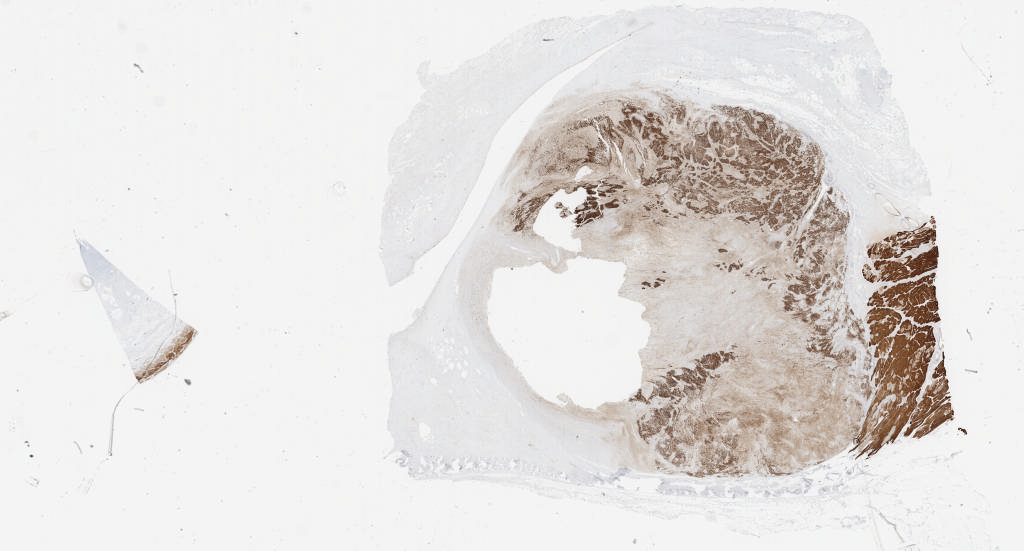

desmin.svs

143423

x

77188

@

40X